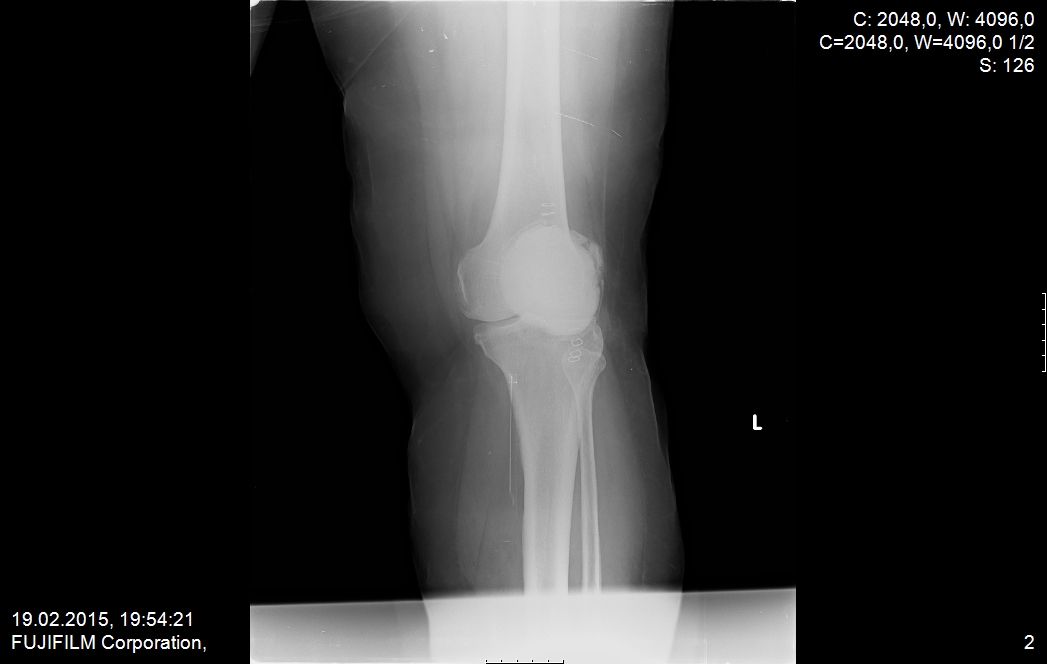

ameliyat öncesi